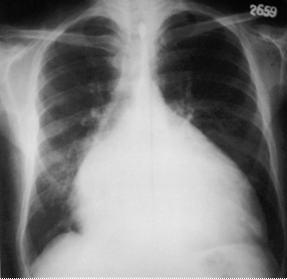

Radiologice (de obicei nerelevante, dependente de cantitatea de lichid din pericard).

Imagine Rx de pericardita acuta

Semne radiologice cardiopulmonare:

cardiomegalie importanta cu contururi net trasate, stergerea arcuatiei normale, cord 'in carafa',

circulatie pulmonara normala.

radiologic: cord de dimensiuni normale cu contur net trasat, eventual cu calcificari pericardice si circulatie pulmonara normala,